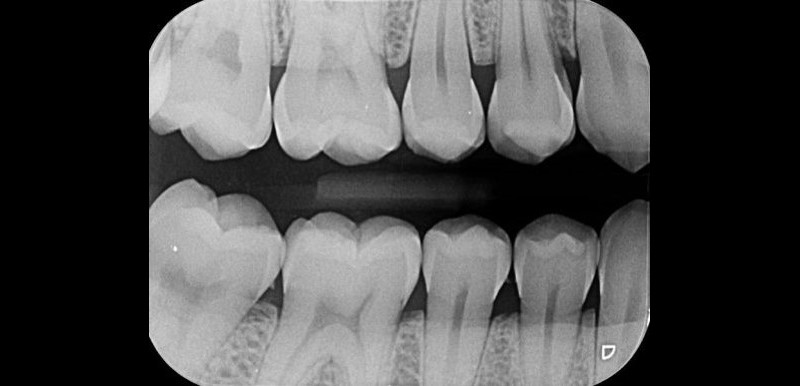

RADIOGRAFÍA

INTERPROXIMAL

Detectar lesiones incipientes a tiempo, permite tratamientos conservadores y evita sorpresas para el paciente.